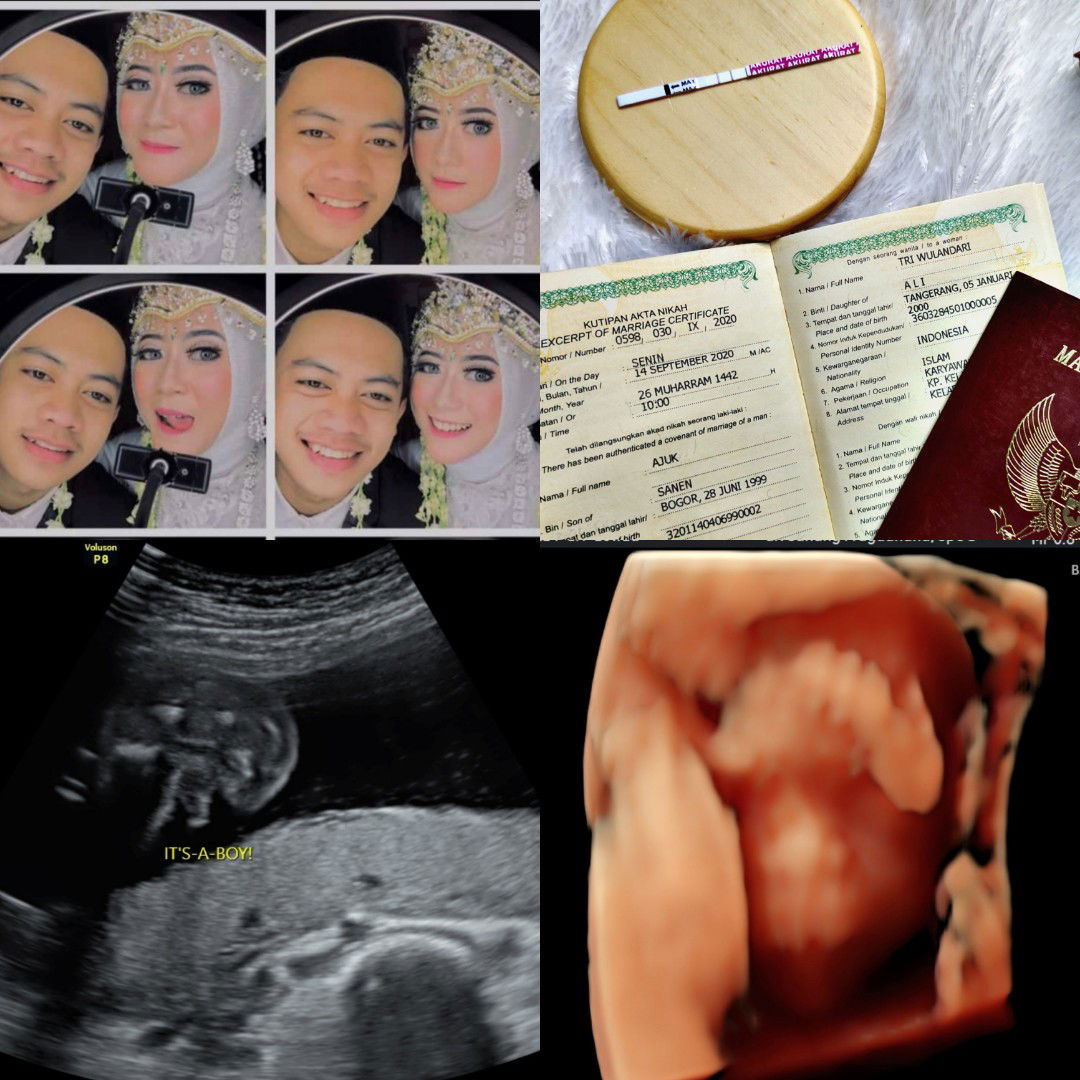

Cara cepat naikin BB janin gimana ya Bun? Yang sudah berpengalaman boleh banget bantu sharingnya

Assalamu'alaikum bunda-bunda.. Mau sharing bunn sekalian minta sarannya,soalnya aku kepikiran bgt Bun janin ku 37w BB-nya cuma 2,5g tiap pagi juga masih suka mual kadang sampe muntah Bun trs BB awal aku juga kecil cuma 37kg ,cara cepet naikin BB janin selain makan daging merah apalagi ya bunn? #pleasehelp #firstbaby #bantusharing #seriusnanya

ibu anak 1